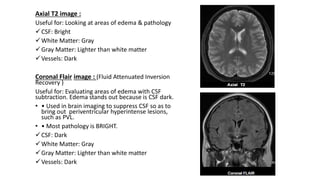

Axial T2 image :

Useful for: Looking at areas of edema & pathology

CSF: Bright

White Matter: Gray

Gray Matter: Lighter than white matter

Vessels: Dark

Coronal Flair image : (Fluid Attenuated Inversion

Recovery )

Useful for: Evaluating areas of edema with CSF

subtraction. Edema stands out because is CSF dark.

• • Used in brain imaging to suppress CSF so as to

bring out periventricular hyperintense lesions,

such as PVL.

• • Most pathology is BRIGHT.

CSF: Dark